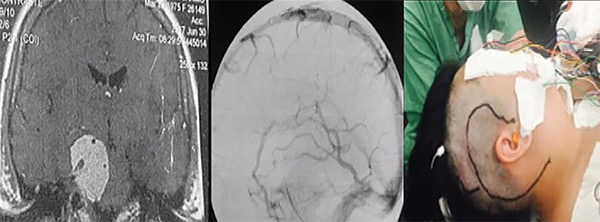

La resonancia magnética muestra la extensión y la relación de la lesión con el tronco encefálico, vasos y pares craneales, demostrando claramente cuando se produce el desplazamiento y la compresión de las estructuras normales. La resonancia magnética con gandolinio a menudo demuestra una lesión con realce intenso y homogéneo. En T1 el tumor tiene un aspecto isointenso, mientras que en TR largo (T2 y Flair) es hiperintenso. Además, es bastante hidratado y tiene una superficie externa ligeramente lobulada. La confirmación de edema en T2 en el tronco encefálico caracteriza la invasión de la aracnoides y generalmente es un signo de mal pronóstico cuando se trata de resecar el tumor por completo.3,4 La resonancia magnética de alta definición es esencial para la planificación quirúrgica. La vascularización del tumor y su relación con los vasos importantes se pueden demostrar mediante angiorresonancia magnética, angio-tomografía computarizada tridimensional multicorte o mediante arteriografía digital. Es importante estudiar el suministro vascular y los desplazamientos, estenosis u oclusiones de las arterias basilar, carótida interna y sus ramas. Incluso en los casos en que la arteria basilar está involucrada por el tumor hay un buen plano de clivaje con éste. Estos tumores generalmente son irrigados por ramas de la arteria carótida externa y por ramas del tronco meningohipofisiario (arteria de Bernasconi- Cassinari) generalmente aumentado.20,21 Los tumores hipervascularizados se pueden embolizar en el período preoperatorio reciente, pero generalmente la coagulación de la base del tumor al comienzo de la cirugía es suficiente para prevenir un sangrado mayor. La ubicación del drenaje de la vena de Labbé es crucial cuando se pretenden llevar a cabo abordajes en los que sea necesaria la retracción del lóbulo temporal, como un abordaje petroso (Figura 3). Su visualización preoperatoria se puede obtener mediante angio-tomografía computarizada - venografía o angiografía de fase venosa. Este conocimiento preoperatorio es muy importante para planificar el abordaje quirúrgico a fin de preservar la vena de Labbé y prevenir complicaciones venosas.22

Los abordajes petrosos son pre-sigmoideo retrolaberíntico, pre-sigmoideo translaberíntico y petrosectomía total. Estos abordajes se utilizan cuando la lesión se encuentra en la fosa media, fosa posterior y la región clivus (Figuras 3 y 4). Si el paciente tiene buena audición previa, se prefiere el acceso pre-sigmoideo retrolaberíntico. Cuando no hay audición preservada es posible extirpar los canales semicirculares, y este abordaje se denomina pre-sigmoideo translaberíntico. Para los tumores gigantes que cruzan la línea media en la región prepontina es necesario un abordaje más lateral y extenso, a través de la petrosectomía total (petrosectomía posterior asociada con la petrosectomía anterior). La cirugía se realiza con el paciente en posición decúbito dorsal, con la cabeza vuelta hacia el lado opuesto. La incisión en la piel se realiza en forma semicircular a partir la región temporal, cuatro centímetros por encima del arco cigomático, pasando tres centímetros detrás de la oreja, extendiéndose dos centímetros detrás de la punta del mastoides. Para evitar fístula del LCR postoperatoria, se utiliza la reconstrucción de la base del cráneo con la fascia temporal, que se diseca con el periostio mastoideo, la fascia craneocervical y el músculo esternocleidomastoideo, que se separa de su inserción, formando un gran colgajo vascularizado que es girado para atrás al final de la cirugía para cubrir todo el campo quirúrgico. La corteza mastoidea es drenada, identificándose el laberinto y el canal del nervio facial. Estos canales no son abiertos. Se realizan dos trepanaciones por encima y dos por debajo del seno sigmoideo y, con una broca de alta rotación, se realiza una craneotomía, exponiendo las fosas media y posterior (retrosigmoide). Los senos petroso superior, sigmoideo y transverso son expuestos. Las celdas mastoideas retrofaciales se eliminan hasta el bulbo yugular. La duramadre anterior es expuesta al seno sigmoideo. Se extraen las células cigomáticas y supralaberínticas, manteniendo intactos los canales semicirculares y el oído medio. El seno petroso superior se secciona anterior a su entrada en el seno sigmoideo. Antes de esta maniobra, debe conectarse con un punto o con microclips. Luego, se realiza una incisión en el tentorio, inicialmente perpendicular al seno petroso superior de dos a tres centímetros y luego medialmente, paralelo al seno transverso en otros tres centímetros. Esta maniobra permite una amplia exposición del cerebelo, separándolo a partir del aspecto posterior del lóbulo temporal en "libro abierto". Se debe tener cuidado para preservar la vena de Labbé, que tiene una anatomía variable y generalmente ingresa al seno transverso diez milímetros antes de su unión con el seno sigmoideo. La evaluación preoperatoria de la anatomía venosa es esencial para planificar este abordaje. La incisión del tentorio se continúa hasta la incisión donde se expone y preserva el IV par craneal. Algunas pequeñas venas puente basales en la base anterior del lóbulo temporal se coagulan y cortan, permitiendo una amplia exposición subtemporal. Se debe evitar la colocación de espátulas fijas con Leyla apoyando el lóbulo temporal y el cerebelo. En general, la espatulación leve realizada por el auxiliar de manera no continua es suficiente para exponer toda la región petroclival de los pares craneales III a VII y VIII. El nervio trigémino generalmente se puede ver desplazado posterior y superiormente. El tumor se desvasculariza por la coagulación bipolar de su inserción dural. Posteriormente, la resección intracapsular fragmentada del tumor se realiza con un aspirador ultrasónico, realizando una citorreducción del tumor, que permite la disección de la cápsula tumoral de los nervios, la arteria basilar y las arterias cerebelosa superior y cerebral posterior. El nervio abducente es muy delgado y frágil. El canal de Dorello se encuentra medial a los pares craneales VII y VIII, y esta región debe abordarse solo después de una resección extensa del tumor. Las extensiones tumorales de la parte posterior del seno cavernoso se resecan después del nervio trigémino. Toda infiltración del hueso petroso y el clivus se elimina con una broca de diamante. Después de la extracción total, la duramadre se cierra herméticamente o con un injerto de fascia y pegamento de fibrina. El abordaje presigmoideo translaberíntico es similar, pero con la eliminación adicional del laberinto al drenar los canales semicirculares, lo que agregará una exposición de aproximadamente 1,5 centímetros de cirugía y permitirá una mejor vista de las estructuras de la línea media. Esta apertura de los canales semicirculares causa sordera y sólo está indicada para pacientes sin audición viable previa.1

Figura 3:Resonancia magnética con gadolinio, corte coronal, que muestra un componente tumoral en la fosa posterior y en la fosa media. Caso ideal para el abordaje petroso (izquierda). Angiografía de fase venosa que muestra drenaje de la vena de Labbé en la unión del sigmoide con el transverso, sin contraindicar el abordaje petroso (centro). Incisión del abordaje petroso (también conocido como abordaje presigmoideo (supra/infratentorial) utilizado en este caso (derecha).

Figura 4: RM coronal con gadolinio que muestra tumor con componente en la fosa posterior y en la fosa media. Caso ideal para el abordaje petroso, también conocido como petrosectomía posterior o abordaje presigmoideo supra/infratentorial (izquierda). Visualización del abordaje antes de abrir la duramadre (izquierda).